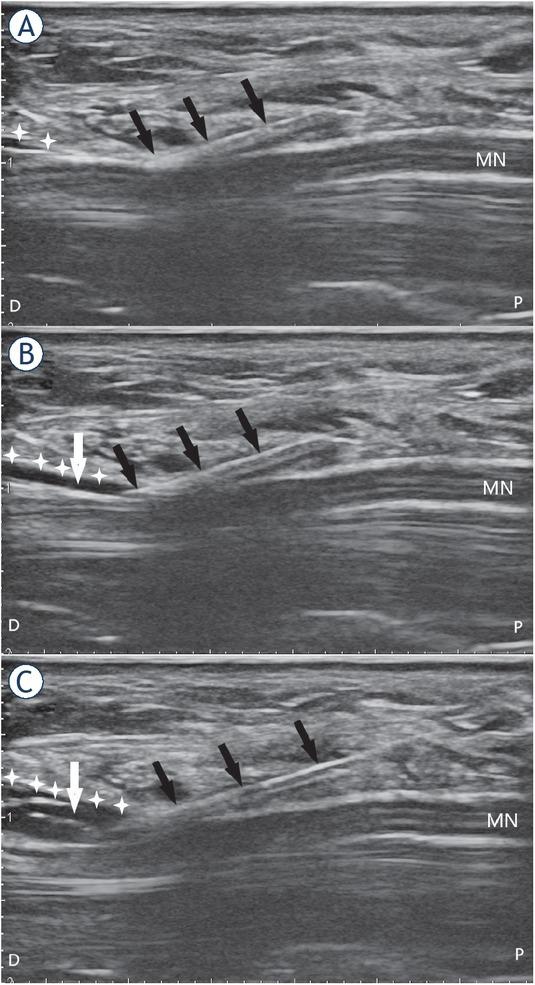

Medications used for carpal tunnel injections are corticosteroids30,31,32,33,34,35, local anaesthetics (LA)35, dextrose36,37, platelet-rich plasma (PRP)25,38, progesterone23,39 and saline.40 The most widely used medications for carpal tunnel injections are corticosteroids30,31,32,33,34,35, which ameliorate MN compression due to their anti-inflammatory properties.3 Particulate (e.g. methylprednisolone) or nonparticulate (e.g. dexamethasone) corticosteroids can be injected in doses of 40–80 mg.30,31,32,33,34,35 The adverse effects of corticosteroids are rare and range from skin discoloration and irritation at the injection site to neurotoxicity and atrophy of thenar muscles.35 Another medication commonly used in the treatment of CTS are LAs35, predominantly short-acting LAs (e.g. lidocaine 2%) that can be injected as a single compound or in conjunction with corticosteroids.28,35 These offer immediate pain relief and may give long-lasting effects, which are speculated to be caused by the blockage of the sympathetic reflex arc, suppression of nociceptive discharge, blockade of sensitization, and anti-inflammatory effects.35 Adverse effects of LAs are rare and range from common allergic reactions to inadvertent intravascular injection, a very serious complication that can lead to seizures and heart conduction blocks.35 More recently, dextrose has also been used as a medication.36,37 The exact mechanism of action of dextrose is not known, but it is thought that it stimulates an anti-inflammatory response through the inhibition of capsaicin, causing sensitive receptors to prevent the release of substance P and calcitonin gene-related peptide, both of which are known to cause swelling of the nerve and induce pain.37 The main advantage of dextrose is that no serious adverse effects due to biochemical properties were reported.37 Saline is widely used either as a single compound in hydro-dissection or as a diluting substance for corticosteroids or LAs (Figure 5A,B,C).30,31,32,33,34,35,40,41 There are no serious adverse effects of saline; however, pain upon injection has been reported when no LA is added.22,28,30,40 A promising type of injectate is PRP25,38 that triggers a neuroregenerative response by releasing several hormones and growth factors, such as platelet-derived growth factor, transforming growth factor, epidermal growth factor, vascular endothelial growth factor, and insulin-like growth factor-1. These stimulate healing by reducing the inflammatory response.38 Lastly, progesterone, which has anti-inflammatory and neuroprotective effects on nerves, has also been used recently as an injectate.23,39

(A), (B), and (C) showing the carpal tunnel in the long axis. The effect of injectate volume on perineural space expansion and subsequent hydrodissection. Note the expansion of the perineural space (white arrow) around the median nerve before (A), during (B) and after injecting 6 ml of the injectate and subsequent hydrodissection (C).

black arrows = needle; D = distal; MN = median nerve; P = proximal; white cross = transverse carpal ligament

There is no consensus on the optimal volume injected into the carpal tunnel and injection volumes anywhere between 1 ml to 10 ml can be found in the literature.30,31,32,33,34,35,37,40,42,43,44,45,46 The injectate can be a manufactured single-compound solution or a multi-compound preparation. The latter is a mixture of active compounds with either saline or LA or both.30,31,32,33,34,35,40,42,43,44,45,46 Corticosteroids are predominantly injected as a multi-compound solution of 1–2 ml corticosteroids with 1–2 ml of LA or 1–2 ml of saline.28,30,31,32,33,34,45,46 LAs are usually added to multi-compound solutions as an anaesthetic during the injection and are rarely injected as a single compound, but when they are, the volume ranges from 0.5 to 4 ml.35,47 Saline is mostly used as a mixture substance for other medications as a part of multi-compound solutions.30,31,32,33,34,35,36,37,40,44,45,46 In hydrodissection, saline is used as a single-compound solution of 3–10 ml in volume.40,48 Dextrose is injected as a single-compound solution of 3–10 ml in volume.37,40,48 PRP is injected as a single-compound solution of 1–3 ml in volume.25,38 Progesterone is injected as a multi-compound solution, a mixture of 0.5 ml of LA and 0.5 ml of progesterone.23,39